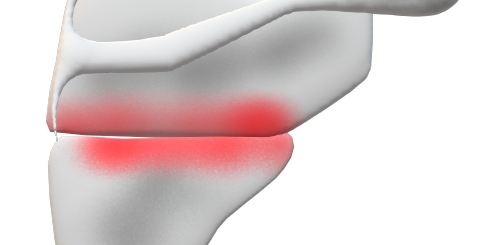

肩関節前方脱臼との鑑別ポイント

| 上腕骨外科頸骨折 | 肩関節前方脱臼 | |

| 肩の膨隆 | 血腫著明 | 膨隆消失 |

| 骨頭 | 肩峰下に触知 | 位置異常 |

| 関節運動 | ある程度可能 | 弾発性固定 |